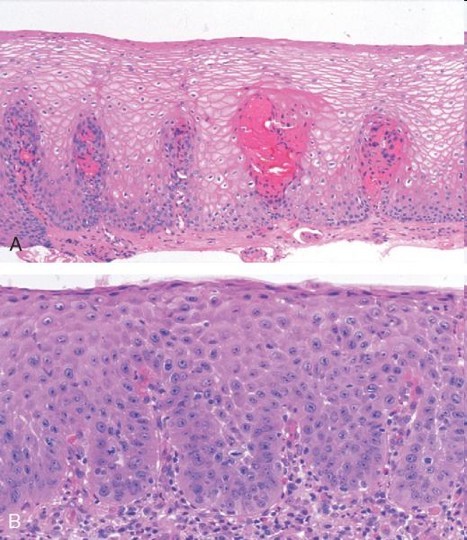

A 55 year old man has had chronic heartburn for the last 20 years that he has “managed” with tums and decreasing ingestion of spicy foods. Upon endoscopic examination, you see the following. What is his diagnosis and what other concerns might you have?

Barrett’s esophagus= Endoscopically recognizable columnar metaplasia of the esophageal mucosa that is confirmed pathologically to have intestinal metaplasia, the latter defined by goblet cells. Complication of longstanding reflux

Both the endoscopic and pathologic components should be present to establish BE

See “salmon pink tongues” (columnar metaplasia) and goblet cells in luminal esophagus= intestinal metaplasia

Below: contrast with normal GE junction: Barrett’s squamocolumnar junction (Z-line) does not correspond to gastroesophageal junction

Development of adenocarcinoma in BE= metaplasia–> dysplasia–> carcinoma sequence (50-fold increase in adenocarcinoma- 5-8% 5-year survival)

* 2% risk in BE pts W/O dysplasia

* 20% risk in BE pts W/ high-grade dysplasia (~45% low-grade dysplasia progress to high grade)